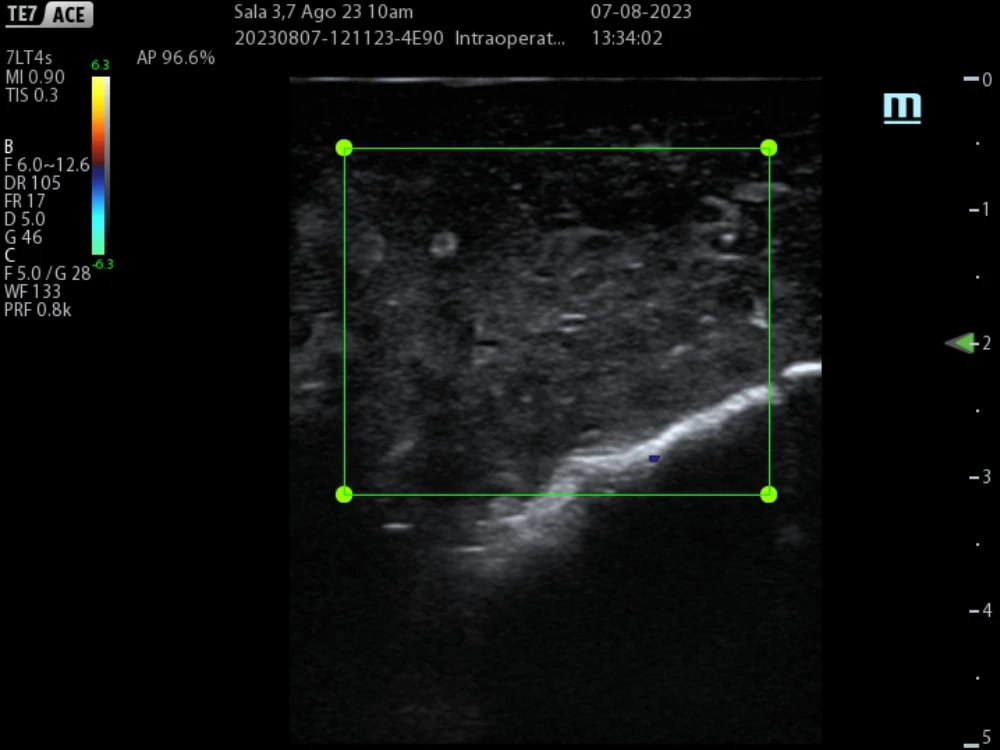

We also use transoperative Doppler to evaluate an adequate Pringle maneuver, which consists of blocking arterial and portal flow transiently to facilitate liver transection and decrease intraoperative bleeding. (Figure 6)

non-crirrhotic-liver-fig6

Fig 6. Doppler ultrasound during Pringle maneuver showing no vascular flow in right liver, prior to transection.